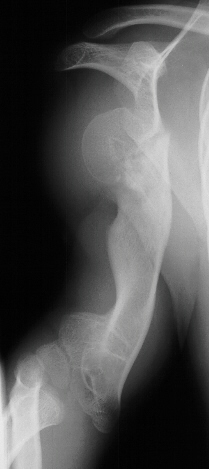

This 3 year boy presented with shortening of the right humerus.

Clinical examination revealed 4 cm shortening of right arm and

painless limitation of ROM of right shoulder; abduction was 150

degrees with 80 degrees at the glenohumeral joint and internal

rotation was significantly limited(image 1). There was also a

of the same knee(image 2). Radiological examination showed absence

of proximal epiphysis of the right humerus(image 1)with marked

deformity of the metaphyseal region. By age 11 the child had a